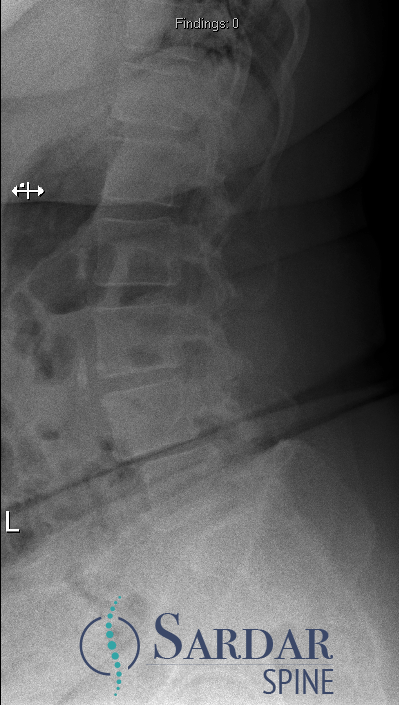

From robotics and AI-driven surgical planning to virtual modeling and custom implants, I’ve embraced a combination of tools that allow me to create tailored surgical plans for my patients—particularly those with scoliosis and spinal deformities.

What sets my approach apart is the seamless integration of these advanced technologies to ensure unparalleled accuracy and better outcomes for each patient.